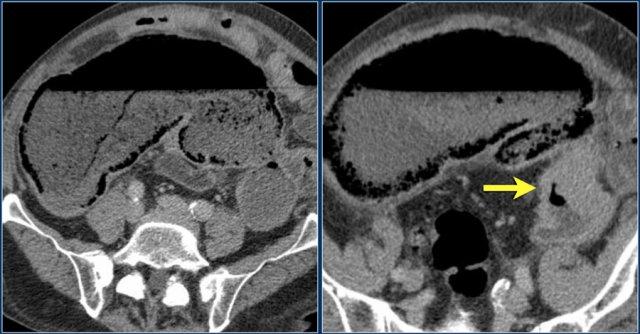

Ruột Sốc

Ở bệnh nhân sốc giảm thể tích, có sự phân phối lại dòng máu.

Điều này có thể dẫn đến hình ảnh ngấm thuốc mạnh bất thường của thành ruột, như trong trường hợp bệnh nhân đang trong tình trạng sốc mất máu này.

Lưu ý một số quai ruột có kiểu hình tăng tỷ trọng (dạng trắng), trong khi các quai khác lại có dấu hiệu bia nước.

Hình ảnh tĩnh mạch chủ dưới dạng khe hẹp là do tình trạng giảm thể tích tuần hoàn (mũi tên đỏ).

Do hệ quả của sự phân phối lại dòng máu ưu tiên đến các cơ quan thiết yếu, những bệnh nhân này có thể có hình ảnh tuyến thượng thận ngấm thuốc quá mức, vì các cơ quan này cần tăng cường sản xuất adrenaline để đáp ứng với tình trạng sốc.